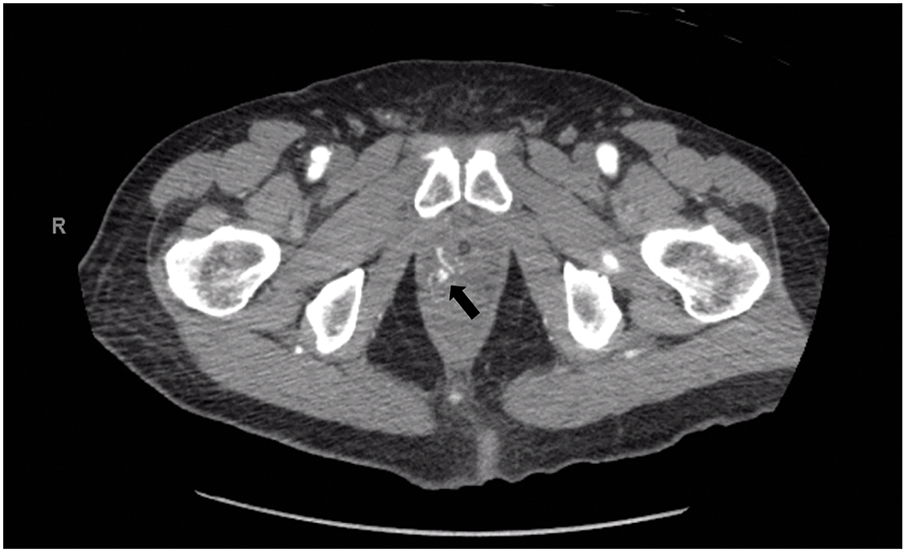

Computed tomography (CT) angiogram of the abdomen and pelvis showed a 4.2 × 7.4 mm pseudoaneurysm of the prostatic artery (Figure 1). He was transferred to UPMC Presbyterian for consideration of pseudoaneurysm embolization. He, however, ultimately declined, citing a “bad feeling” about going forward with the procedure. He had no further bleeding episodes and was discharged home in stable condition. His biopsy results demonstrated that all cores were positive for prostate adenocarcinoma, maximum grade Gleason 4 + 3 = 7, and >50% core involvement. Extraprostatic extension and perineural invasion were noted. He was referred to the medical oncology team at UPMC Shadyside to discuss treatment options.

FIGURE 1. Computed tomography (CT) angiogram demonstrating right prostatic artery pseudoaneurysm. The arrow indicates the site of the pseudoaneurysm